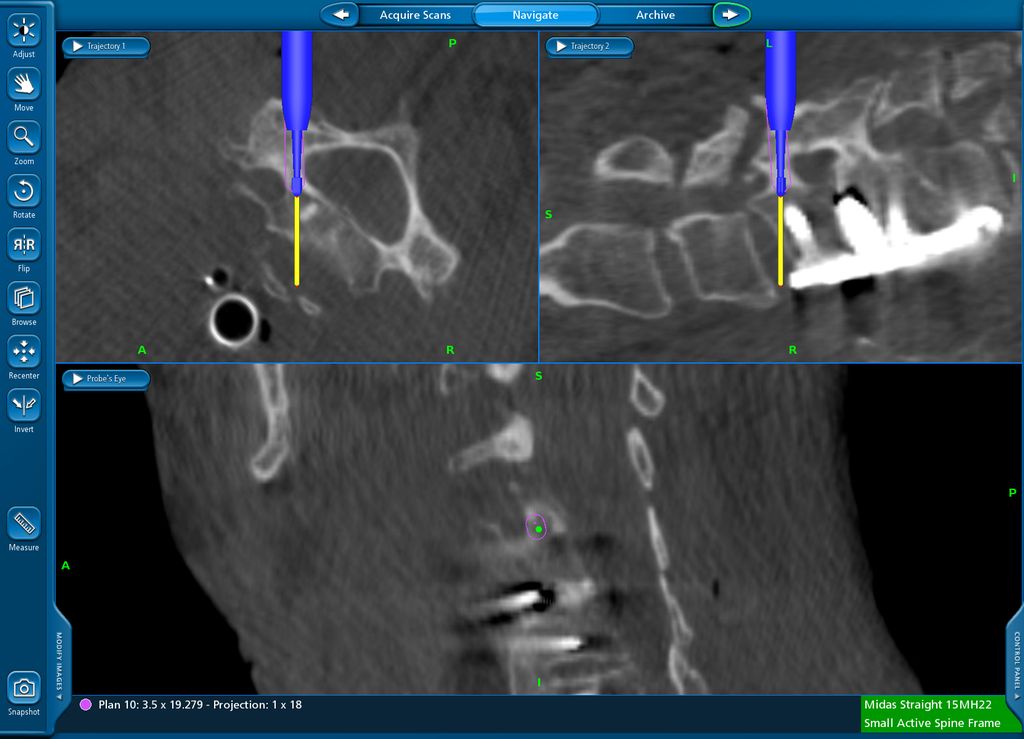

Navigierte Implantation eines „interbody device“ über lateralen Zugang (XLIF; „Xtreme lateral interbody fusion“). Bei der 79-jährigen Patienten kam es nach Fusion L4/5 vor mehr als 10 Jahren zu einer symptomatischen Anschlusssegmentdegeneration L3/4 mit Schmerzen im Dermatom L4 beidseits sowie zu Lumbago. Es erfolgte navigiert die Implantation eines Zugangs in Rechtsseitenlage. Intraoperativ wurde die Referenz am Beckenkamm platziert (Abb. 12) und mit intraoperativem CT (O-Arm) ein 3D-Datensatz gewonnen. Anhand dessen können Instrumente wie Küretten oder Raspatorium (Abb. 13) wie auch die Implantation des Cages selbst (Abb. 14) navigiert werden. Das postoperative Röntgen zeigt einen regelrechten Implantatsitz (Abb. 15).